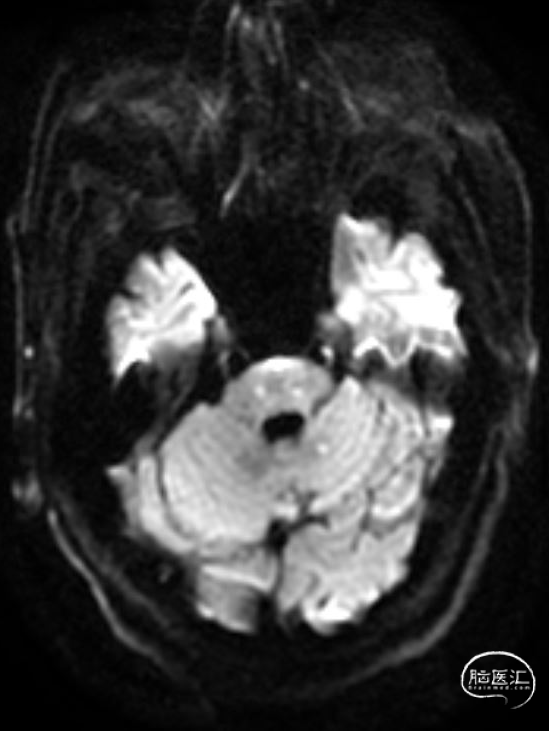

➢2023年10月31日

头颅MRI平扫:脑桥、左侧小脑半球、颞叶多发急性/亚急性脑梗死。